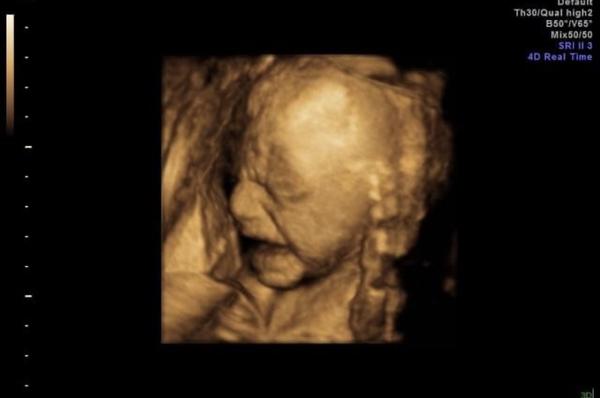

My byli na 3D/4D na konci 28.tt a syn byl obličejem otočený směrem do břicha. Čtvrt hodiny mi doktor třepal s břichem, ať se milostpán pohne. Kdeže 😂. Odcházeli jsme s touto fotkou, víc se nenatočil.